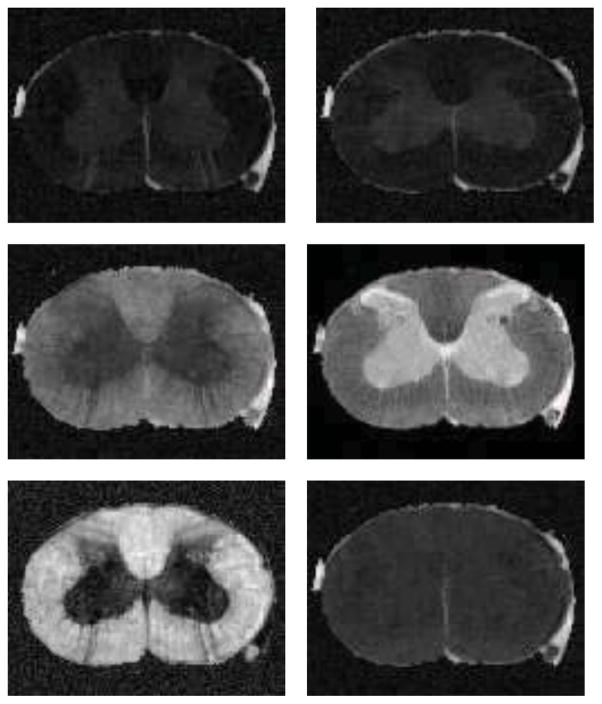

We also did DTI estimation on a 100 × 80 × 32 × 52 3D rat brain DWI. The data was acquired using a PGSE technique with TR=1.5s, TE=28.3ms, bandwidth=35Khz, 52 diffusion weighted images with a b-value of 1334s/mm2.

We compared with several other methods on the DTI estimation, however, to save space, we only show the results of MRE, LMMSE and our proposed method. We present D11, D22, D33, S0, FA, and mean trace for each estimated result. The DTI estimation results of MRE, LMMSE and our proposed method are shown in Fig. 3, 4 and 5 respectively.

Figure 3.

From left to right, top to bottom are D11, D22, D33, S0, FA, and mean trace of the estimated tensor field using MRE on the rat cord data set.

Figure 4.

From left to right, top to bottom are D11, D22, D33, S0, FA, and mean trace of the estimated tensor field using LMMSE on the rat cord data set.

Figure 5.

From left to right, top to bottom are D11, D22, D33, S0, FA, and mean trace of the estimated tensor field using our proposed method on the rat cord data set.